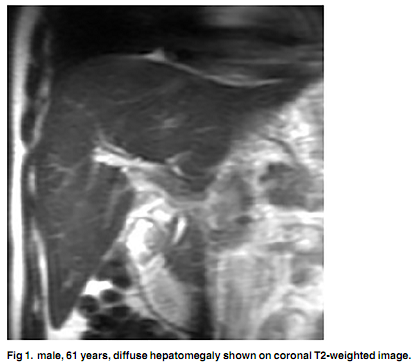

研究人员分析了2009年至2013年间在中国首都医科大学附属北京友谊医院或北京妇产医院曾进行MRI检查的45例患者。包括38例女性和7例男性(平均年龄51.3± 9.7岁),其中33例患者也进行了肝活检。

MRI显示,25例患者呈门静脉周围高信号,8例呈I期和II期均匀肝脏信号强度,以及25例呈非均质肝脏信号变化。组织学分级和肝脏信号强度不一致之间存在正相关(P <0.001)。

“MRI可可靠的检测PBC一般指征,如肝肿大,脾肿大,门静脉主干扩张,门脉侧支循环和腹水,”研究人员得出结论称。“MRI是诊断PBC的一种有价值的方法,门脉周围晕征程度和肝脏信号强度有助于评估肝纤维化程度。” - Melinda Stevens